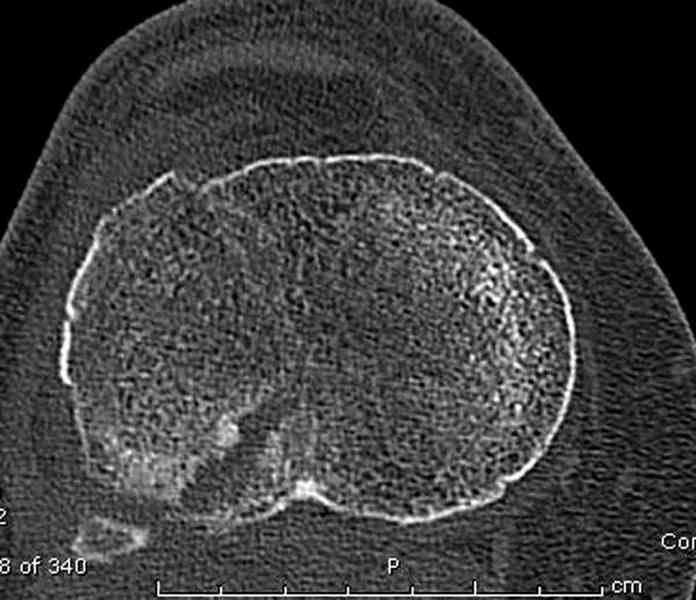

Касаемо перелома мыщелка, лучше сделать СКТ и после определиться с операцией. Фиксировать - проксимальной поддерживающей пластиной. Есть хорошие варианты. Чтож до дистальной части - аппарат кроме стабилизации ничего не даст. Если 6 кг вытяжения не расколотили отломки, то при открытом доступе вся эта мелочь вывалится. По-моема операцию следует рассматривать с позиции подготовки к артродезу (ось выправить, осколки попытаться собрать). Ну и готовить морально пациентку к неработающему голеностопу.

Для внутрисуставных переломов необходимо идеальное сопоставление, а такая задача без КТ срезов усложнится. Только КТ надо делать после дистракции сустава, иначе нельзя получить объективную информацию.

Пациентки прооперирована, результат чего на снимках. Выполнена открытая репозиция костей правой голени, синтез малоберцевой пластиной, б/берцевой винтами, имеющиеся фиксаторы не подходили, было принято решение репонировать отломки, синтез винтами, гипсовая повязка.

В данный момент локально отёк тыла стопы незначительный, двигательня функция сохранена, ограничена болевым синдромом. Пульсация артерий ослаблена, соответствует левой ноге. Рана - в области границы с пузырём область некроза 2.5*2 см, сухой, не увеличивается, под ним чувствительность сохранена. Чувствительность по всей поверхности кожи в норме, гипоестезия пальцев, при чём варьирует от нормальной, до почти анестезии в течении дня.

Репозиция внутрисуставных переломов неудовлетворительная и не адекватна.

сценарий и для перелома наружного мыщелка б.б.- передний фрагмент стоит на месте, а задний не репонирован - в таком положении оставлять фрагменты нельзя, суставная поверхность должна быть реконструирована.

При наличии менее агрессивных методов (аппарат) попытка под любым предлогом установить “из того что было в наличии”, и тем более при отсутствии показаний, не считается "благородным делом". Упрямство в лечении внутрисуставных переломов не в интересах больного, и привело к неудовлетворительной фиксации.

В лечении переломов пилона восстановление длины малоберцовой является индикатором и ориентиром для успешного лечения. Первый этап восстановления по длине не удался, малоберцовая остается короткой, и репозиция суставной поверхности осталась неудовлетворительной. Длина передней колонны не восстановлена, а в дистальном фрагменте имеется флексия. Оставлена без внимания потеря кости в метафизе. Шурупы 4.5 мм будут выступать после спадения отека, и возможно будут причиной мягкотканого осложнения в гипсе.